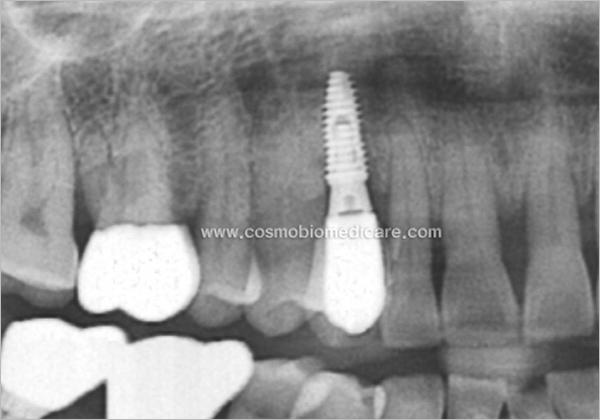

Clinical Cases

• Case1

• Case2

• Case3

• Case4

• Case5

• Case6

• Case7

• Case8

• Case9

• Case10